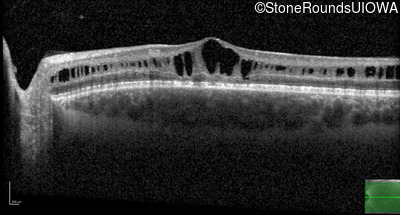

Age at visit: 13 years

Age at visit: 15 years

Age at visit: 17 years

Age at visit: 18 years